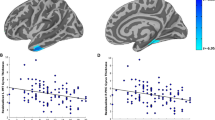

Since the result of the stepwise multiple linear regression indicated that the HAM-D score was associated with the volumes of hippocampus and amygdala in the TBI group, we conducted partial correlation analyses adjusted for the effect of age to further investigate the relationships between hippocampal/amygdalar volumes and the HAM-D scores. Consequently, we found that left hippocampal volume was negatively correlated with the HAM-D scores (r = − 0.27, p = 0.05) and left amygdalar volume showed a positive correlation with the HAM-D scores (r = 0.28, p = 0.04) in the TBI group (Table 7, Figs. 1 and 2).

Scatterplots between HAM-D score and hippocampal volume in veterans with TBI. Abbreviations: HAM-D, Hamilton Rating Scale for Depression; PTSD, Post-Traumatic Stress Disorder. Age was used as a covariate in all analyses. The solid lines represent the line of best fit for the data and the dotted lines indicate the 95% confidence interval

Scatterplots between HAM-D score and amygdala volume in veterans with TBI. Abbreviations: HAM-D, Hamilton Rating Scale for Depression; PTSD, Post-Traumatic Stress Disorder. Age was used as a covariate in all analyses. The solid lines represent the line of best fit for the data and the dotted lines indicate the 95% confidence interval

To investigate whether these results were dependent on the lifetime diagnosis of PTSD, we examined the relationships between hippocampal/amygdalar volumes and the HAM-D scores, adjusted for the effect of age in the TBI - PTSD and TBI + PTSD subgroups. There was a significant negative correlation between left hippocampal volume and the HAM-D score in the TBI + PTSD subgroup (r = − 0.39, p = 0.03). However, in the TBI - PTSD subgroup, the HAM-D scores were not related to left hippocampal volume (r = − 0.30, p = 0.15). The HAM-D scores were not significantly correlated with right hippocampus and bilateral amygdala in the TBI + PTSD and TBI - PTSD subgroups (Table 7, Figs. 1 and 2).